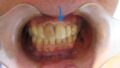

今日のインプラントオペは下顎左側6番のケースです。

初期固定も良いので1回法で仕上げました。